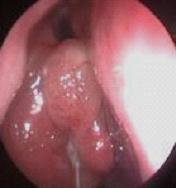

鼻炎长期得不到有效治疗导致鼻息肉以及鼻腔囊肿

经常鼻塞、流脓鼻涕、头痛多为鼻窦炎、鼻息肉等。